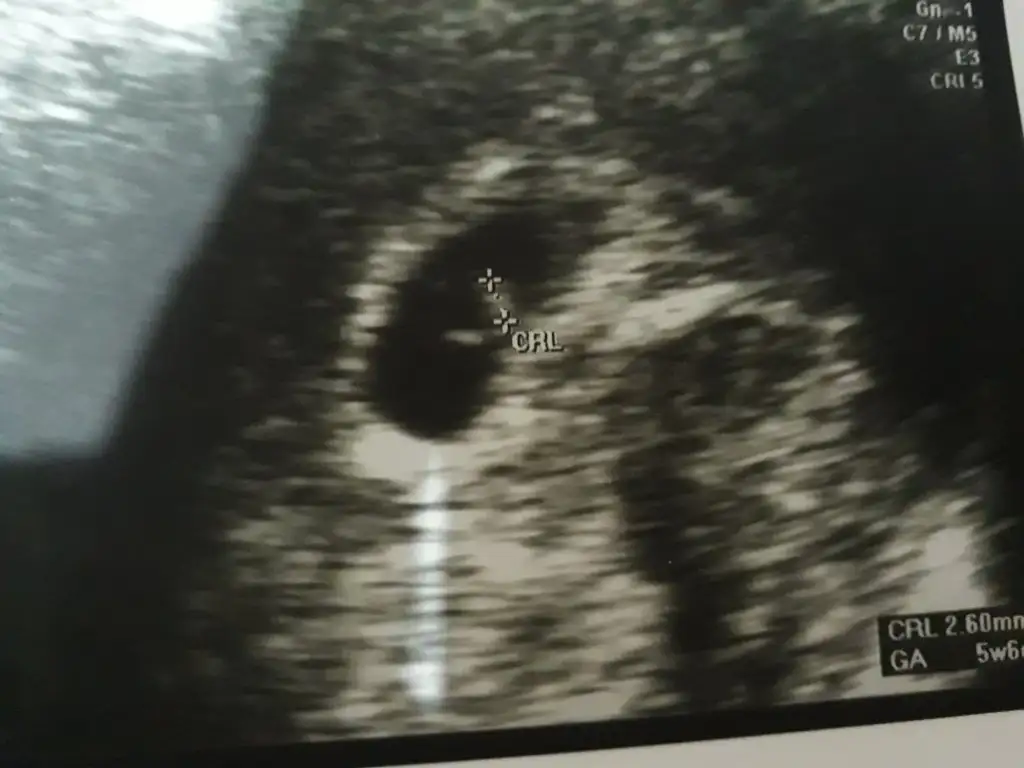

canım toksoplazma ve igg gibi vücut direnci olan şeyler haric hepsini sağlık ocağı yapıyo. tsh kan sayımı vitaminler idrar testi gibileri sağlık ocağında yaptırdım ama diğeri mecbur devlet hastanesindeKızlarr.çıktık doktordann şükürler olsn herşy yolnda ... kalbinide duydk minnoşun...yalnz doktor benden toksoplazma idrar kültür kan sayımı falan istedi..sağlk ocagı yapıyo mu hepsni doktr bildiğim kadaryla yapmıyo devlete gideblirsn dedi ama malum randevu 10 gün sonra